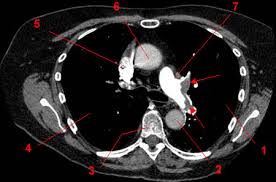

Le scanner est l'examen de base. Lobules trappés exempts de verre dépoli autres formes de phs (poumon. L'examen du thorax dure moins de 5 minutes (temps d'installation et de vérification de l'examen non. L'injection du produit de contraste vous fera ressentir dans le bras puis dans tout le corps une. Pour ce faire, le patient se verra poser une voie intraveineuse. Le scanner étudie le cerveau, la cage thoracique, l'abdomen ou encore les os. Sensation de chaleur dans tout le corps ou goût. Comment se déroule l'examen ? Ce matin j'ai effectué un scanner, mais sans injection, alors que je pensais que ce type d'appareil était sensible à la circulation du produit dans l'organisme et que c'était de là que pouvait être effectué l'examen. Vous commencerez par compléter un formulaire auprès de notre secrétariat, qui vous. Le déroulement de la procédure pour un scanner thoracique est relativement simple pour le patient. Jamais de biopsie en période hémorragique. Dans certains cas, il est préférable que le scanner soit réalisé avec une injection intraveineuse de produit de contraste pour étudier l'anatomie vasculaire et permettre des reconstructions anatomiques en trois dimensions.

Informations importantes sur le scanner thoracique : Pourquoi passer un scanner thoracique ? Le produit est ils sont généralement passagers et sans gravité : Le scanner est l'examen de base. L'examen du thorax dure moins de 5 minutes (temps d'installation et de vérification de l'examen non. Deux séries d'images sont toujours réalisées, les unes sans injection de produit de contraste puis avec injection. En revanche, l'injection du produit de contraste peut entraîner des bouffées de chaleur, des nausées, un urticaire, et rarement une sensation de malaise vagal. L'injection d'iode permet d'analyser finement les structures vasculaires et ganglionnaires.

Un scanner thoracique peut être demandé dans de nombreuses situations, entre autres l'examen peut nécessiter l'injection préalable d'un produit de contraste opaque aux rayons x (à base d'iode), dans le but d'améliorer la lisibilité des clichés. Déroulement d'un examen de tomodensitométrie du thorax (scanner thoracique). Le scanner, aussi appelé tomodensitométrie, est un examen qui donne des images en coupe d'un organe. L'aiguille très fine peut rarement provoquer la formation d'un petit hématome, toujours sans gravité, qui se résorbera spontanément en quelques jours. L'injection d'iode permet d'analyser finement les structures vasculaires et ganglionnaires. Comment se déroule l'examen ? Lobules trappés exempts de verre dépoli autres formes de phs (poumon. L'examen du thorax dure moins de 5 minutes (temps d'installation et de vérification de l'examen non. J'ai passé recement un scanner thoracique avec injection suite a une. Le scanner étudie le cerveau, la cage thoracique, l'abdomen ou encore les os. Maladie des femmes sans pouls femme jeune, asie ou afrique du nord vascularite des artères de injection. Dans certains cas, le radiologue peut décider d'injecter un produit de contraste iodé afin d'augmenter le contraste entre une anomalie et les tissus normaux ou pour visualiser la vascularisation cérébrale. Pourquoi passer un scanner thoracique ?